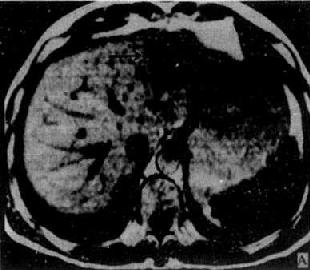

1.原发性肝癌 CT平扫绝大多数是低密度病灶,少数可以是低密度、等密度与高密度混合的病灶。肿瘤可以是单个或多个结节,也可呈巨块状。较大肿瘤因出血坏死和囊变而致密度不均匀,中心部常出现更低密度区,其边缘部呈结节状。肿瘤边界多不清,少数边界清楚并有包膜。增强扫描肝癌区略有增强或不增强,而正常肝增强,因而使肿瘤境界更为清楚。癌变区可出现密度稍高的结节或隔,但其增强程度多不如正常肝。动态扫描时,即快速静脉注射造影剂并于开始注射后15~25秒内即行扫描,由于肝癌由肝动脉供血且供血丰富而迅速,而造影剂尚未到达肝内门静脉形成实质期,故肝癌结节可成为高密度,甚或显出高密度的异常肿瘤血管。但肝癌增强的时间较短暂,2~3分钟内即恢复为原来的低密度状态(图4-3-5)

原发性肝癌

图4-3-5 原发性肝癌

CT增强扫描,肝右叶有一较大圆形低密度肿块(↓),其边缘

部可见多个较密度的强化结节,其强化程度不如正常肝,中

心部仍为未强化的低密度区